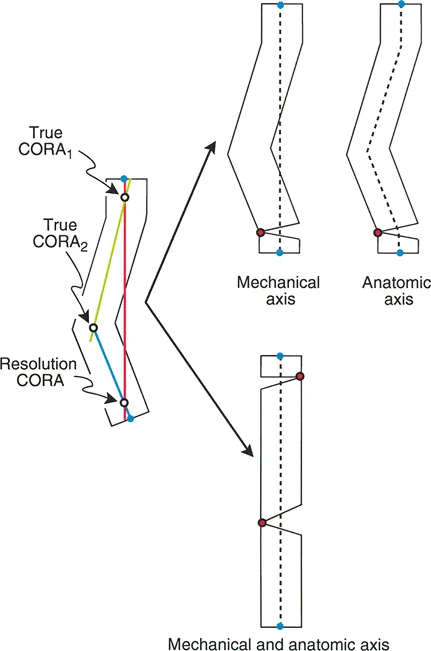

مركز دوران الانحراف (CORA)

يعتبر CORA خاصية أساسية للتشوه في العظم. يُعرّف بأنه نقطة تقاطع خط المحور الميكانيكي (أو التشريحي) القريب وخط المحور الميكانيكي (أو التشريحي) البعيد.

* CORA الحقيقي: هو القمة التشريحية الفعلية للتشوه.

* CORA الحل (Resolution CORA): نقطة نظرية تُستخدم في التشوهات متعددة المستويات حيث تتقاطع المحاور القريبة والبعيدة النهائية، وقد لا تقع هذه النقطة داخل العظم نفسه.

محور تصحيح الزاوية (ACA)

بينما يعتبر CORA حقيقة تشريحية ثابتة، فإن ACA يقع جزئيًا تحت سيطرة الجراح. يمثل ACA النقطة المحورية التي يدور حولها الجزء البعيد من العظم لتحقيق التصحيح.

* الموضع الأمثل: يجب أن يكون ACA موجهًا بشكل عمودي على مستوى التشوه ويمر مباشرة عبر CORA.

مستوى قطع العظم (Osteotomy Level)

مستوى قطع العظم (الشق الجراحي) يقع بالكامل تحت سيطرة الجراح. تحدد العلاقة الهندسية بين مستوى قطع العظم، وACA، وCORA النوع الدقيق للتصحيح الناتج، وتحدد ما إذا كان سيحدث تشوه ثانوي غير مقصود (مثل الانزياح غير المرغوب فيه).

إن فهم العلاقة المكانية بين القطع، والمفصلة، وقمة التشوه هو سر التصحيح الخالي من العيوب. تحدد قواعد بالي لقطع العظم النتائج الميكانيكية لخطتك الجراحية:

القاعدة الذهبية الأولى: القطع والمفصلة عند مركز الانحراف

عندما يمر كل من قطع العظم وACA مباشرة عبر CORA، يتم تصحيح التشوه الزاوي بشكل مثالي. يتم استعادة المحور الميكانيكي، ولا يوجد انحراف في المحور الميكانيكي (MAD)، وتبقى أجزاء العظم القريبة والبعيدة متوازية تمامًا. هذا هو السيناريو المثالي، والذي غالبًا ما يتحقق بقطع عظم وتدي بسيط (فتح أو إغلاق) عند قمة التشوه.

القاعدة الذهبية الثانية: المفصلة عند مركز الانحراف والقطع بمستوى مختلف

في بعض الأحيان، قد يكون قطع العظم مباشرة عند CORA غير ممكن سريريًا بسبب سوء حالة الجلد، أو وجود أدوات جراحية سابقة، أو مشاكل في جودة العظم في منطقة الكردوس/الجذع. إذا بقي ACA عند CORA، ولكن تم إجراء قطع العظم عند مستوى مختلف (أقرب أو أبعد عن CORA)، فسيتم تصحيح التشوه الزاوي بالكامل. ومع ذلك، ستنزاح نهايات العظم عند موقع قطع العظم بالنسبة لبعضها البعض.

* النتيجة السريرية: يؤدي هذا إلى "نتوء" أو تعرج في المحور التشريحي، لكن المحور الميكانيكي العام وتوجيه المفصل يظلان متوائمين تمامًا.